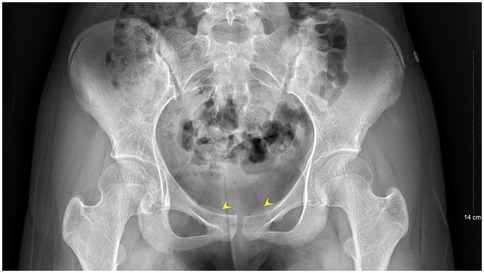

A 13-year-old female presented to the Department of Pediatrics at Dongguan Maternal and Child Health Hospital with a 10-day history of intermittent fever and pain in the pubic symphysis region. The patient denied a history of pelvic surgery, local trauma, or strenuous exercise. Her past medical and family histories were unremarkable. Between February 10 and 18, 2025, she was hospitalized at an external institution due to pubic symphysis pain, restricted lower limb mobility, and high fever. Blood cultures identified the presence of methicillin-resistant Staphylococcus aureus (MRSA) and she was treated initially with cephalosporins and penicillins which resolved the fever but only partially alleviated the pubic pain. Upon transfer to our hospital, physical examination revealed stable vital signs, no fever, localized tenderness and swelling over the pubic symphysis without erythema or fluctuance, bilateral restricted hip motion (aggravated by adduction and abduction), and an antalgic gait. The laboratory findings included a white blood cell count of 6.08 × 109/L (neutrophils: 64.0%), procalcitonin <0.1 ng/ml, and an erythrocyte sedimentation rate (ESR) of 80 mm/h. Blood cultures confirmed the presence of MRSA. Although intravenous antibiotics had resolved the fever, pubic pain and mobility limitations persisted, particularly with limited hip mobility, notably painful external rotation and adduction, where external rotation was less than 15 degrees and adduction was less than 10 degrees. Consultation with orthopedic specialists led to the suspicion of pubic symphysis infection, prompting an MRI examination. The imaging revealed infection of the pubic symphysis with bilateral osteomyelitis and a small abscess in the posteroinferior muscle layer (Figures 1, 2). Based on these clinical manifestations, laboratory results, and imaging findings, the diagnosis was confirmed as pubic symphysis infection with bilateral osteomyelitis and abscess formation.

Figure 1. Preoperative MRI indicates infection of the pubic symphysis.

Infection of the pubic symphysis is a rare but serious condition, with early symptoms often being nonspecific and easily overlooked. Patients typically present with pain in the pubic symphysis region, which worsens with movement of the hip joint, restricting mobility and leading to limping. However, these clinical manifestations lack specificity and can be easily confused with other postpartum or postoperative pelvic conditions, such as pubic symphysis diastasis, non-infectious osteitis pubis, pubic symphysis injury, and pubovesical fistula. Additionally, especially in the early stages of the disease, significant bone destruction may not be visible on imaging examinations, further complicating diagnosis. MRI is the imaging modality of choice for diagnosing pubic symphysis infection. Its high-resolution soft tissue imaging capabilities enable the early detection of inflammatory changes, such as bone marrow edema, widening of joint spaces, and inflammatory infiltration of the surrounding soft tissue. In cases where infection is suspected, microbiological tests (e.g., blood or pus cultures) should be performed to identify the causative pathogens. Early MRI evaluation to distinguish infectious from non-infectious lesions can prevent disease progression, including sequestrum formation, abscess development, fistula formation, bilateral pubic ramus bone destruction, and loss of pelvic stability (11). In the present case, the patient's x-ray examination was unremarkable, whereas MRI revealed the presence of bilateral pubic osteomyelitis and an abscess in the posterior muscle layer of the pubic symphysis, further supporting the anatomical basis for the spread of infection in this region. Therefore, in high-risk patients, such as those with fever, and significantly elevated CRP levels and ESR, MRI should be performed even if initial x-ray findings appear normal to avoid misdiagnosis and delayed treatment. In terms of pathogen classification, pubic symphysis infections can be categorized into three types, namely, non-specific (e.g., Staphylococcus aureus), specific (e.g., Mycobacterium tuberculosis), and mixed bacterial infections. Mycobacterium tuberculosis is the most common pathogen responsible for specific bacterial infections and diagnosis is based on its isolation from pus or biopsy tissue. The primary treatment consists of anti-tubercular therapy, with surgical intervention considered in cases of extensive sequestrum formation, fistula development, and failure of conservative management, with generally favorable outcomes (12). Non-specific bacterial infections show similar presentations to non-infectious osteitis pubis, with the key distinguishing feature being an acute onset with fever. Common pathogens include Staphylococcus aureus, Pseudomonas aeruginosa, Escherichia coli, Salmonella species, and anaerobes. However, standardized diagnostic and treatment guidelines for these infections are lacking (13). The primary treatment approach involves pathogen-specific antibiotic therapy, with surgical intervention considered in selected cases. However, there is no consensus on the optimal timing for surgery, and the surgical techniques used vary widely. Common surgical approaches include thorough debridement, local placement of antibiotic beads, holmium laser debridement, or fixation of the pubic symphysis in refractory cases (1417).